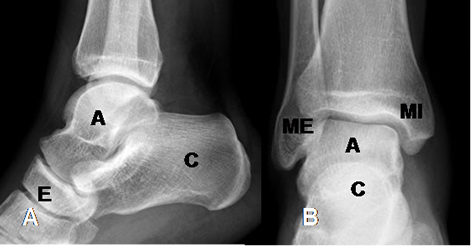

Estructuras óseas a tener en cuenta: Maléolo interno y maléolo externo, huesos del retropie (Calcáneo y talo o astrágalo), huesos del mediopie (Escafoides, cuboides, cuneiformes medial, medio y lateral) y huesos del antepie (Metatarsianos y falanges).

(Fig 4 A y B).

Fig 4 A. Tobillo normal.

A: Rx lateral y B: Rx AP. C: Calcáneo. A: Astrágalo o talo. E: Escafoides.

MI: Maléolo interno. ME: Maleolo externo.